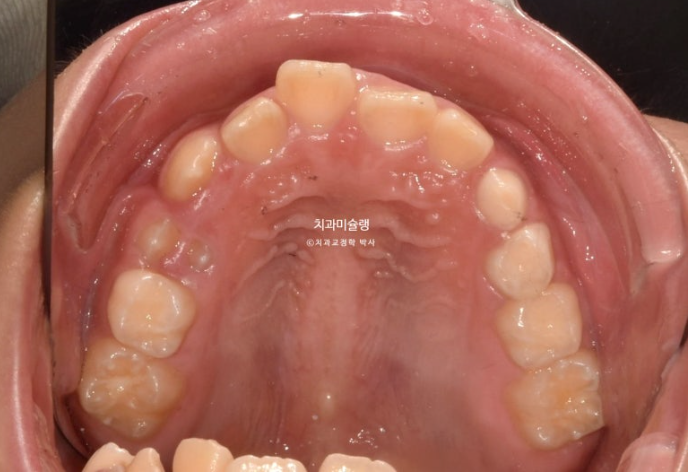

영구치날 공간은 비교적 양호한 편입니다.

파란화살표 자리에 있어야할 작은어금니가 선천적 결손 상태입니다.

이런 경우 계승영구치가 없어 오래도록 남아있게될 잔존유치를 최대한 보존해서 쓰는 방법으로 치료를 합니다.

잔존유치를 오래 보존해서 사용하기로 했다면 교정 치료 중 불필요한 치아이동에 의해 잔존유치치근이 녹아 짧아지지 않도록 각별히 신경써야 합니다.

유치는 교정력을 받았을때 영구치와 다르게 잘 움직이지 않을 뿐더러, 안그래도 영구치에 비해 뿌리가 약한 상태이니 치근흡수라도 나타나면 발치해야 하는 애매한 상황이 생깁니다.